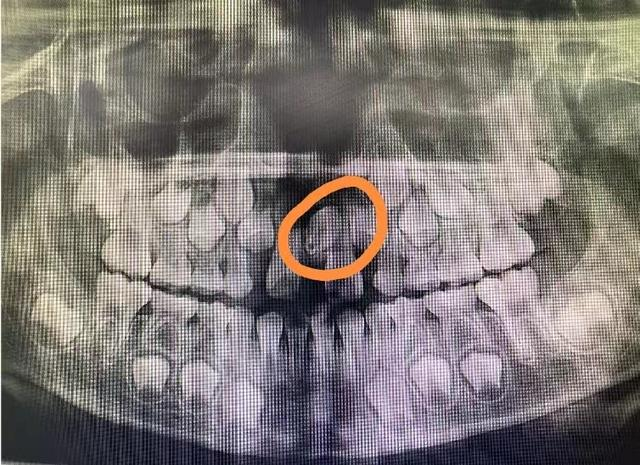

医生,我们片子拍好了,有问题吗?

小朋友家长,这是刚拍好的片子,请看这个地方,是因为长了多生牙才影响了正常恒牙的位置,导致两颗牙齿之间的间隙过大。

多生牙已经造成了恒牙的间隙过大,需要拔除。你家小朋友的多生牙倒着长还埋伏在骨头了,拔除难度较大,建议预约口腔外科或者微创拔牙门诊进行拔除。到时候还需要拍个CT确定它的三维位置,和周围牙齿的关系。

2.埋伏的多生牙通常在治疗其他疾病如牙髓炎等拍摄X线后偶尔发现,此时往往没有任何临床表现或者症状。对于未萌或者阻生的多生牙,如果现阶段没有妨碍相邻牙齿的发育和萌出,没有囊肿存在的证据,可暂时观察,待患儿足够大,有了更好的耐受力时(通常5周岁左右)方手术拔除。